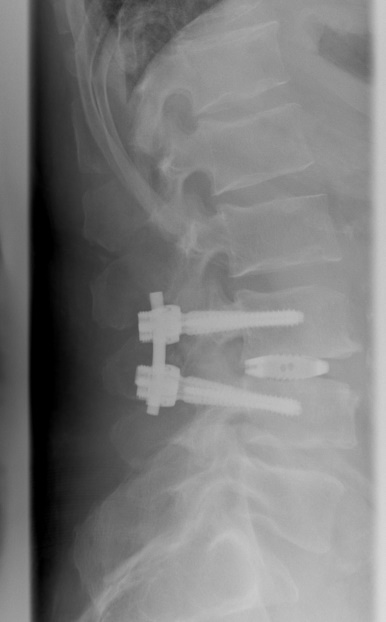

Dynamische Neutralisation/Kombinationsverfahren

Bei rein degenerativer Erkrankung einer Bandscheibe ohne Mitbeteiligung der Facettengelenke und ohne krankhafte Veränderung der Nachbarwirbel ist die dynamische Neutralisation des Segmentes möglich. Kombinationsverfahren mit Versteifung und dynamischer Neutralisation können gegebenenfalls sinnvoll sein.

Beispiel Dynamische Neutralisation/Kombinationsverfahren